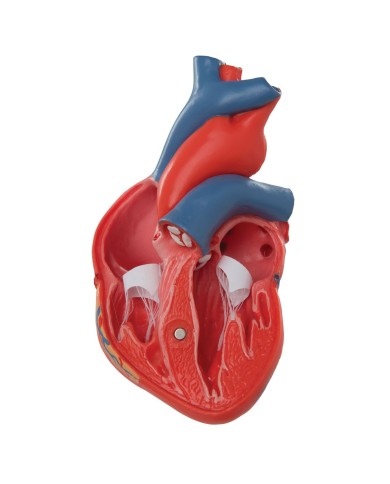

Modello di cuore di alta qualità scomponibile in 5 parti

Modello di cuore di alta qualità scomponibile in 5 parti

La parete anteriore del cuore è staccabile per poter vedere i ventricoli.